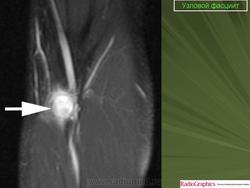

Узловой фасциит.

Нодулярный фасциит(син.: инфильтративный фасциит, узловатый фасциит, псевдосаркоматозный фиброматоз, нодозный фасциит, пролиферирующий фасциит, псевдосаркоматозная дерматофиброма) - самая частая узловая форма псевдосаркоматозной пролиферации реактивной природы. Развивается в глубоких слоях дермы, подкожной клетчатке, иногда в мышцах. У 10-15 % больных нодулярному фасцииту предшествует травма. Чаще болеют мужчины, преимущественно в возрасте 20-40 лет. До 20 % больных - дети. Локализация: голова, шея, ладонная поверхность предплечья, грудная клетка, спина, зоны по ходу периферических артерий и вен (у детей). В зависимости от локализации выделяют краниальный и внутрисосудистый фасциит, а также другие родственные формы фасциитов и миозитов.

Макроскопически нодулярный фасциитпредставляет собой нечетко отграниченный узел диаметром 1-5 см, на разрезе серовато-белый или пестрый, иногда с участками ослизнения. Не малигнизируется, рецидивирует крайне редко. Под микроскопом обнаруживаются многоклеточные, короткие или длинные пучки, состоящие из коллагеновых волокон и веретеновидных, иногда звездчатых фибробластов с вытянутыми ядрами. Пучки имеют S- или С-образную форму. Волокна внутри пучков могут иметь беспорядочную ориентацию или параллельное расположение. Встречаются муаровые структуры. В ядрах фибробластов хорошо видны ядрышки, можно найти фигуры митоза. Иногда обнаруживаются гигантские многоядерные клетки, налом инаюшие остеокласты. В связи с гистогенезом нодулярного фасциита из мио-фибробластов в клетках определяется экспрессия ряда «мезенхимальных» маркеров: с одной стороны, гладкомышечных антигенов - некоторых актинов (SMA и MSA), виментина и CD68 (КР1), с другой - кластера дифференцировки гистиоцитов CD56. Кроме того, в разных участках новообразования выявляются зоны ослизнения и мелкие кровоизлияния. В ряде случаев имеет место гиалиноз коллагеновых пучков. Нодуллярный фасциит следует отличать от пролиферативного фасциита, пролиферативного миозита, фибромы, фиброзной гистиоцитомы, нодулярного теносиновита, веретеноклеточной фибросаркомы.